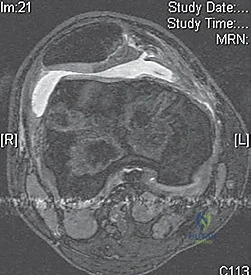

- MRI Scan: Highly recommended for all patients with a large traumatic effusion due to the high rate of occult articular or osteoarticular injury.

* Osteochondral Lesions: Crucial for determining size, location, and potential for repair versus removal.

* Bone Bruise Pattern: Confirms patellar dislocation (medial patella and lateral femoral condyle).

* Anatomical Risk Factors: Assesses patella alta, trochlear dysplasia, tibial tubercle-trochlear groove (TT-TG) distance.

* Bone Bruises: MRI often reveals increased signal on the medial patella and the midportion of the lateral femoral condyle. This distinct pattern helps differentiate it from ACL tears.